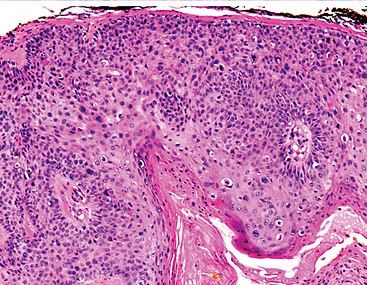

Merkel cell carcinoma made headlines with the death of Jimmy Buffett. It’s rare and dangerous, and cases are becoming more common.

"Margaritaville" singer-songwriter Jimmy Buffett died four years after receiving a diagnosis of Merkel cell carcinoma that "can be really nasty," one expert tells CURE.

This FDA approval of Zynyz was based on findings from a study which demonstrated that the therapy improves responses in patients with locally advanced Merkel cell carcinoma.